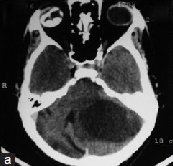

由于高度怀疑为恶性肿瘤,通过上开颅术对颅内视神经进行活检,诊断为间变性星形细胞瘤(who3级)。图3:肿瘤切除后3个月(甲)和6个月(乙)的视神经照片显示视神经头的椎间盘新生血管和...